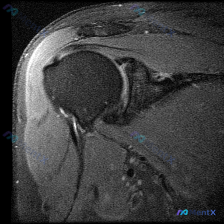

本来找盂唇病变?这张肩关节MRI的阅片陷阱90%的人会踩

整理了一份肩关节MRI的病例资料,临床申请的检查目的是排查盂唇病变,不过仔细阅片后发现核心异常好像不在盂唇那边?

- 序列修正:初始标注为T1序列,实际影像符合质子密度压脂(PD FS)或T2压脂序列特征,对积液、肌腱损伤敏感

- 核心可见表现:肱骨大结节处肌腱信号异常、连续性中断,肩峰下区域存在明显高信号积液